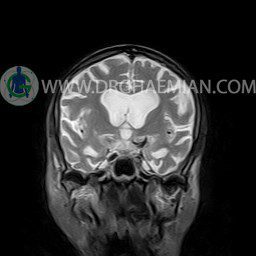

ام آر آی گوش (کانال شنوایی داخلی) یک روش تصویربرداری غیر مداخله ایی و بدون دردی است که با استفاده از امواج رادیویی و میدان مغنایسی قوی تصاویری با جزییات از کانل استخوانی که اعصاب و عروق خونی را از مغز به گوش داخلی می برد ایجاد می کند. در این کیس ماستوئیدیت سمت چپ دیده می شود.

INTERNAL AUDITORY CANAL MRI

(without contrast)

Technique: axial – coronal T1 , coronal T2 , Axial FLAIR .

The vestibulocochlear nerve on each side shows normal course and diameter .

The cochlea and semicircular canals appear normal .

– Hyperintensity in left transverse & sigmoid sinuses suggestive for venous stasis & thrombosis

– Fluid in left mastoidal cells suggestive for mastoiditis

are seen